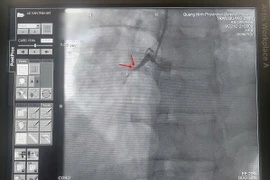

Kỹ thuật Mini Crush là tái thông lòng mạch bị hẹp ở cả hai nhánh chính và phụ được tối ưu, giúp giảm triệu chứng đau ngực và suy tim ở bệnh nhân có tổn thương vị trí chia đôi của động mạch vành.

Nhờ chuyển giao kỹ thuật từ Bệnh viện Đại học Y Hà Nội, Bệnh viện Đa khoa tỉnh Quảng Ninh đã thực hiện thành công ca phẫu thuật bắc cầu động mạch chủ và động mạch vành kèm thay van tim nhân tạo cho bệnh nhân bị hẹp động mạch liên thất trước và hở van hai lá.